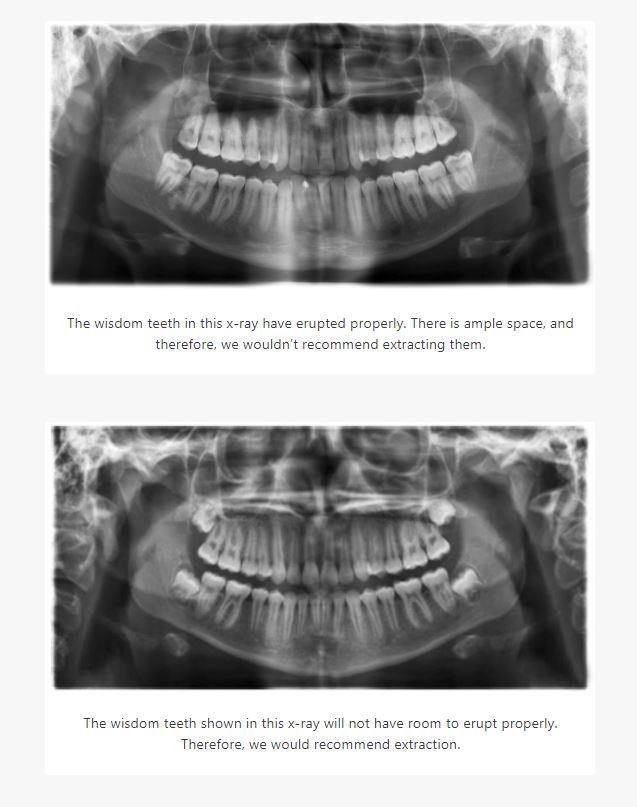

It’s very common for wisdom teeth to become impacted, which simply means that they don’t erupt the way they should. There may not be enough room in your jaw, or the angle of entry is wrong.

If a wisdom tooth is impacted, we need to remove it as soon as possible, as it will undoubtedly cause serious problems for you. You may develop gum tenderness or notice swelling and pain. In some cases, even if your wisdom teeth erupt properly, we may recommend extracting them.

If you’re thinking about having your wisdom teeth removed, it’s best to do it as soon as possible. The younger you are, the less likely these teeth have fully formed roots, which means removing them will be much easier. Your recovery time will also be reduced significantly. If you’re not sure whether you should remove your wisdom teeth, the best thing to do is to have x-rays taken. That will help us make a recommendation one way or the other.

No, not always. More often than not, wisdom teeth cause serious issues (such as putting pressure on adjoining tooth/nerve, or causing crowding leading to unaligned teeth, pain, or infection). But some people have ample room for the wisdom teeth to erupt and never have them extracted. In that case you simply treat them like any other molar.​

We can tell you when or if you need your wisdom teeth removed by taking a panoramic/scan x-ray. But typically before that happens, a patient will feel soreness/tenderness on the gum tissue in the area that the wisdom teeth are located. This pain is usually caused by them trying to erupt. Once they start moving to erupt you should call us for an appointment. (Remember, generally there is not enough room for them to fully erupt, so don’t wait that long!)